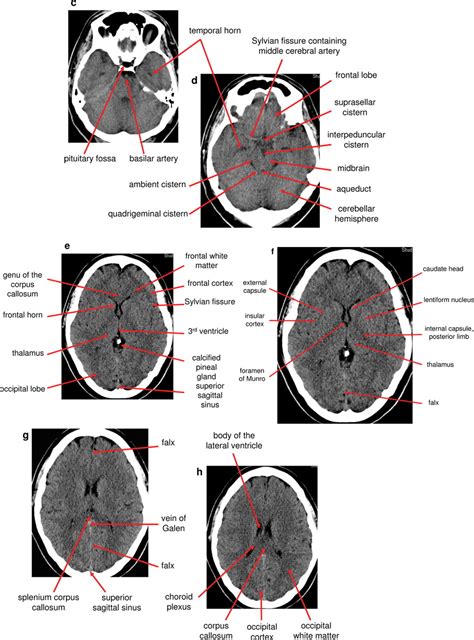

Medical imaging technologies such as functional neuroimaging, and electroencephalography (EEG) recordings are important in studying the brain. The medical history of people with brain injury has provided insight into the function of each part of the brain. Neuroscience research has expanded considerably, and research is ongoing.